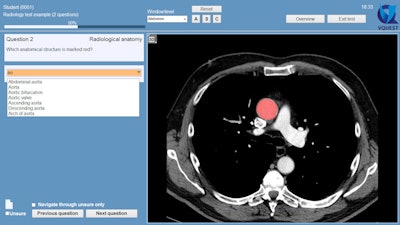

Example of an "indicate question" in VQuest. The student is asked to mark an anatomical structure in the volumetric image. Students can scroll through the image, change contrast settings manually or with the preset window/level menu, or change viewing direction by clicking the buttons (A, S, and C). The teacher decides which manipulation tools the students are allowed to use during the test or for a particular question. All images courtesy of Dr. Cécile Ravesloot.

Example of a question in which students are asked to name the marked structure. In this case, they need to choose from a long list of options, which they can only open by typing at least two letters of their answer. All alternatives including these two letters are then shown, and the student can click on the preferred answer. This allows for automatic answer checking.